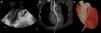

A 27-year-old woman was admitted to our center after emergency vascular surgery for spontaneous dissection of the left iliac artery. Congenital factor VIII deficiency and family history of complicated brain aneurysm were previously reported. Hemoperitoneum and hemothorax were identified after surgery as consequences of a severe coagulation disorder and the patient suffered cardiac arrest with pulseless electrical activity. A portable echocardiograph detected pericardial effusion and emergency blind subxiphoid pericardiocentesis was performed with recovery of pulse. An urgent cardiology evaluation was subsequently required. Transthoracic echocardiography views were severely limited, so it was decided to undertake transesophageal echocardiography. This revealed a catheter crossing the aortic valve to the ascending aorta (Figure 1A). Contrast-enhanced computed tomography angiography confirmed the intravascular placement of a drainage with its distal tip in the proximal segment of the left carotid artery (Figure 1B). The ventricular insertion point was in the anterior interventricular groove, close to the distal segment of the left anterior descending coronary artery (Figure 1C). Prior to entering the operating room, the patient suffered a new cardiac arrest and resuscitation maneuvers were ineffective. Subsequent autopsy revealed systemic vascular and tissue fragility (spontaneous liver and spleen lacerations, aortic rupture and hyoid bone fracture with minimal procedural manipulation), compatible with a diagnosis of type 4 Ehlers-Danlos syndrome.

Figure 1.

Multimodality imaging of the path of the pericardiocentesis catheter crossing the aortic valve to the ascending aorta. (A) Two-dimensional transesophageal echocardiogram, left ventricular outflow tract projection; (B) computed tomography curved format reconstruction along the catheter; (C) three-dimensional volume-rendered computed tomography reconstruction of the catheter insertion point and its relationship with the anterior descending artery.